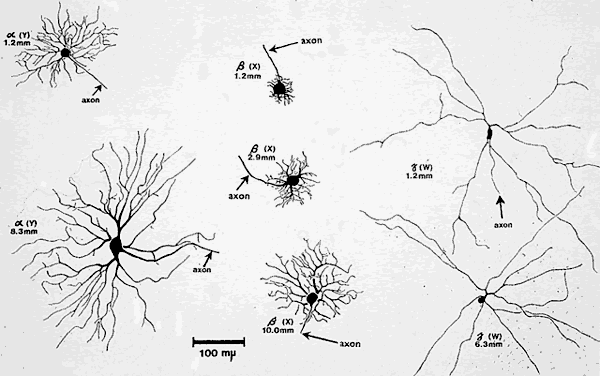

GANGLION CELL INPUT

Although it appears that the pupillary and visual systems share the same photoreceptor input (and presumably bipolar cell input), the role of ganglion cell input is far less clear. Over the years, many anatomic and physiologic studies have been carried out in an attempt to classify retinal ganglion cells based on the their cell body size, dendritic field, axonal diameter, and electrical firing properties. This information has been collected in a number of species, most notably the cat and monkey, and the projections of the cell axons to the lateral geniculate body and midbrain have been studied with the use of labeling techniques. Loewenfeld24 summarized the properties of the major classes of ganglion cells in the retina and their projections. Based on these studies, there appear to be three main types of ganglion cells that make up the retina in primates: the alpha, beta, and gamma cells. In the cat, these correspond to the Y, X, and W cells, respectively (Fig. 11).

Fig. 11. Size and shape of three chief types of retinal ganglion cells (cat), as described by Boycott and Wässle in 1974. All drawings are to the same scale, shown at the lower edge. The numbers given for each cell indicate its distance from the center of the central area of the retina. Alpha cells correspond to Y or “brisk-transient” cells (left), beta cells to X or “brisk-sustained” (middle), and gamma cells to W or “sluggish” cells of other terminologies (right). Note that the dendritic trees of the alpha and beta cells increase in size with eccentricity, but those of the gamma cells do not. The dendritic configurations differ markedly among the three groups of cells and are much smaller in beta cells than in alpha and gamma cells. (Boycott BB, Wässle H: The morphological types of ganglion cells of the domestic cat's retina. J Physiol 240:397, 1974)

Table 2, from Loewenfeld,24 summarizes all of the main properties of the gamma cells (W cells). These cells appear to be the major contributor to the pretectal neurons in the midbrain serving the classic pupillary light reflex pathway. These cells may also play a role in other visually evoked reflexes (e.g., eye position control) projecting to the superior colliculus and also to the accessory optic system. The gamma cells have small cell bodies and thin, slowly conducting axons with large receptive fields. They respond primarily to incremental changes in light intensity and are relatively insensitive to movement. These cells project almost exclusively to the midbrain and not to the lateral geniculate nucleus. They have the highest density in the central field and become less dense in the periphery, which accounts in large part for the central field weighting of pupillary response. The proportion of gamma ganglion cells that serve the pupillary light reflex is not currently known, and the answer awaits specific labeling studies in primates. Such studies are technically difficult to perform, because the retrograde label must be microinjected into the specific pretectal area where light-responding neurons can be identified with the use of electrical recordings. Even then, the label reaching the retinal ganglion cells is only weakly visible; once identified in flat mount preparations, a micropipette must be used to inject these individual neurons with a more visible dye that fills each cell body, dendrites, and axon. It is currently unknown how many retinal ganglion cells project directly to the pretectal midbrain neurons serving the pupillary light reflex, but their number must be relatively small (on the order of 1%) in proportion to the total number of ganglion cells.